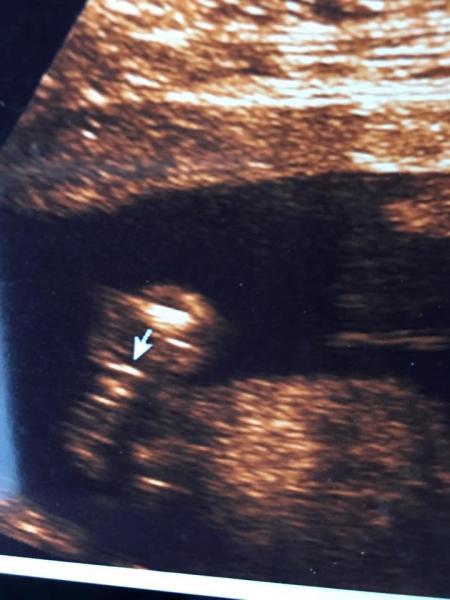

und hier die 3 Striche = Mädchen

Bild zu